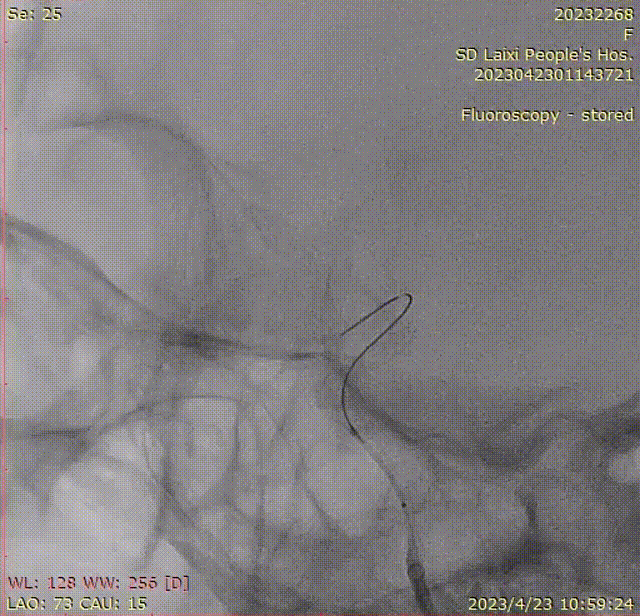

3)释放Nuva®密网支架:

Nuva®密网支架完全释放后,手推造影剂观察显示支架贴壁良好,动脉瘤造影剂残留明显,遂直接回撤输送导丝并撤出通路系统结束手术。